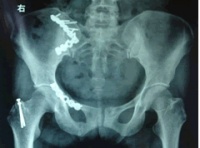

(1)骨盆后前位X线片:X线平片检查一般可明确骨折部位骨折类型及其移位情况,亦常能提示可能发生鵻的并发症。全骨盆后前位X线片可显示骨盆全貌对疑有骨盆骨折者应常规拍摄全骨盆后前位X线片以防漏诊对骨盆后前位X线片上显示有骨盆环骨折者,为明确了解骨折移位情况还应再摄骨盆入口位和出口位片。(2)骨盆入口位片:患者仰卧,X射线从颅侧投向尾侧,与片盒成60°倾斜摄片本位片可显示耻骨段骨折移位;骨盆向内、向外旋转和向内移位的程度;骶髂关节向后移位及骶骨骨折是否侵犯椎管;同样可显示坐骨棘撕脱骨折。

(3)骨盆出口位片:X线是从尾侧投向颅侧,与片盒成45°角本片可显示桶柄型损伤与耻骨体骨折,对确定半骨盆有无向上旋转移位是很有用的,在本片上同样可显示骶骨或髂骨骨折移位情况。

CT检查对骨盆骨折虽不属常规但它可在多个平面上清晰显示骶髂关节及其周围骨折或髋臼骨折的移位情况,因此凡涉及后环和髋臼的骨折应行CT检查骨盆三维重建CT或螺旋CT检查更能从整体显示骨盆损伤后的全貌,对指导骨折治疗颇有助益但应铭记对血流动力学鵻不稳定和多发伤患者,后前位全骨盆X线片是最基本和最重要鵻的放射学检查不要在拍摄特殊X线片上花费时间,更为重要的是尽快复苏。